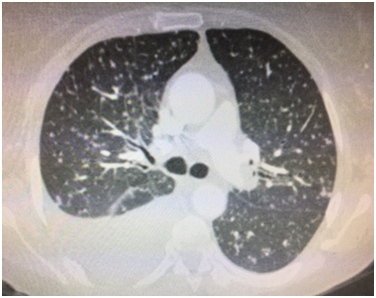

A 57 year old Caucasian female was admitted for dry cough, fever, loss of appetite and chest pain for three weeks. She had a history of tonsillectomy, ankylozing spondylitis, uveitis, pelvis fracture and tibia fracture. Her father died of colonic carcinoma. Her mother had hypertension and previous pulmonary tuberculosis. The patient was under treatment with certolizumab, methotrexate, and prednisolonefor ankylozing spondylitis and uveitis. Daily 300mg isoniazid was also given simultaneously with certolizumab for prophylaxis. Initial laboratory findings revealed WBC 8.2X103/mm3, hemoglobin 10.8g/dl, platelets 341X103mm3, lymphocytes 1.4X103/mm3, creatinine 0.74mg/dl, AST 18IU/L, ALT 18IU/Lmm3, LDH 167IU/L, albumine 3.56gr/dl, CRP 18.6 mg/dl, and calcium 9.1 mg/dl. ECG showed sinus ryhtm. Tuberculin test was negative. Chest x-rayshowed diffuse miliary nodules, alveolar infiltration in the right lower lobe, and right pleural effusion (Figure 1). Pleural protein 4.57g/dl, LDH 353U/L, and albumin 3.56g/dl. Pleural fluid had 1540cells/mm3 with a 74% lymphocyte ratio. Pleural fluid ADA was 114U/L (normal 0-40 U/L). The pleural fluid was exudative compatible with tuberculosis. Computed tomography of the thorax revealed diffuse miliary nodules, infiltration in the right anterior segment of the lower lobe, and right pleural effusion (Figures 2-4). Sputum stains was positive for acid-fast bacilli. Mycobacterium tuberculosis was isolated from the sputum culture. The final diagnosis was miliary tuberculosis associated with certolizumab occuring on the third month of treatment. The patient was commenced on pyrazinamide, isoniazid, rifampicine, and ethambutol treatment for tuberculosis while certolizumab treatment was stopped.

Figure 3 Axial computed tomography showing diffuse miliary nodules and right pleural effusion at the tracheal level.